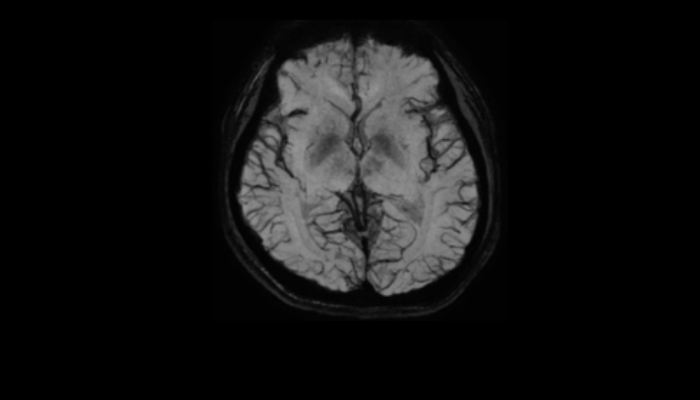

頭部MRI画像 頭部MRI脳腫瘍や脳梗塞、認知症など脳の病気を詳細に評価します。 MRA画像 頭部MRA造影剤を使わずに脳の動脈を描出します。動脈瘤や狭窄を検索します。 脊椎MRI画像 脊椎MRI椎間板ヘルニアや脊柱管狭窄症など脊椎や脊髄の疾患を評価します。 腹部MRI画像 上腹部MRI・MRCP肝臓・胆のう・膵臓・腎臓などの上腹部の重要臓器を詳細に評価します。 乳房MRI画像 乳腺MRIマンモグラフィや超音波と併せて、乳がんを検索や病変の範囲を評価します。 前立腺MRI画像 前立腺MRI前立腺がんを検索します。PSA高値の方はまず前立腺MRIをお勧めします。 子宮・卵巣MRI画像 子宮・卵巣子宮筋腫や子宮体癌、卵巣腫瘍など女性特有の病気を評価します。 膝関節MRI画像 膝関節膝関節の骨や靭帯、半月板を評価します。靭帯断裂や半月板損傷などレントゲンでは評価できない構造も診断できます。 肩関節MRI画像 肩関節肩関節の骨や腱、靭帯を評価します。腱板断裂や腱の断裂などレントゲンでは評価できない構造も診断できます。 心臓MRA 心臓MRA狭心症、心筋梗塞の原因となる冠動脈の狭窄を評価します。造影剤を使用せず、撮影可能です。 DWIBS画像 DWIBS全身のがんを広く検索します。リンパ節や転移の評価にも優れます。